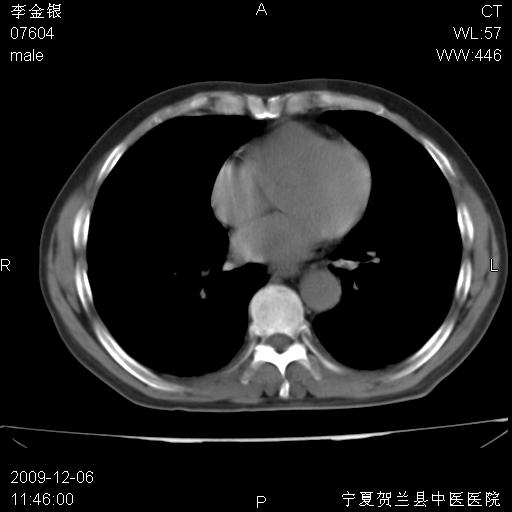

该病人 ,男,62岁,主因咳痰带血两天

考虑右肺中央型占位性病变并阻塞性肺炎.(右肺上叶支气管变窄),建议支纤镜检查.

考虑右肺中心型肺癌伴阻塞性肺炎及右肺门淋巴结转移,建议纤维支气管镜进一步检查。

支气管壁明显增厚 管腔狭窄,腔静脉后多个淋巴肿大,结合年龄病史考虑右肺上叶中央型肺癌并阻塞性肺炎

右肺上叶后段支气管阻塞,右上肺门占位,相应肺段阻塞性肺炎,右肺门有淋巴结肿大。诊断右肺上叶中心型肺癌,阻塞性肺肺炎、右肺门淋巴结转移。

右上叶支气管狭窄,管壁增厚,远端斑片状软组织影,病灶邻近叶间裂,叶间裂无移位。

诊断右肺中央型肺癌。

那个片影应该大部分都是病灶,病灶沿肺段支气管分支生长,后段完全显示不清、闭塞。若为不张应该伴有叶裂的移位,若为炎症应有空气支气管征。

右肺中心型肺癌伴阻塞性肺炎及右肺门与纵膈淋巴结转移很典型,可纤维支气管镜进一步检查

考虑右侧中央型肺癌伴右肺上叶后段阻塞性炎症、肺不张、右肺门和纵隔淋巴结肿大。

右肺上叶中心型肺癌,阻塞性肺炎、右肺门和纵隔淋巴结转移。